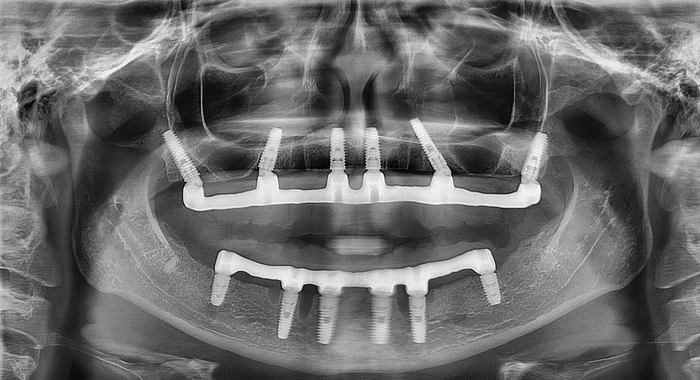

Кейс стоматолога-хирурга, имплантолога Сидорова Данила Владимировича

Стоматологи часто сталкиваются с ситуацией, когда пациенты обращаются за помощью только тогда, когда терпеть боль становится невозможно. Каждый врач принимает решения, основываясь на своем опыте и интуиции, ведь одна и та же проблема может быть решена различными методами. Предлагаемый к рассмотрению кейс интересен тем, что требует всестороннего подхода из-за своей сложности — нам пришлось одновременно решать функциональные и эстетические задачи.

Пациентка: женщина, 38 лет

Елена долго откладывала восстановление улыбки - частичное отсутствие зубов, пародонтит, страх перед сложным вмешательством. Она решилась на первый шаг — записалась на онлайн-консультацию в клинику ESTETUS.

Врач стоматолог-хирург, имплантолог Сидоров Данил Владимирович оценил клиническую ситуацию пациентки и составил план лечения.

Доктор установил ей постоянную конструкцию All-on-6 с немедленной нагрузкой за 3 дня на обе челюсти.

Описание данного клинического кейса мы бы разбили на три отдельные «истории»:

• первая «история» –диагностика и консультация,

• вторая «история» –сначала подготовка к имплантации: профессиональная гигиена, удаление несостоятельных зубов и затем сразу же установка имплантов,

• третья «история» – фиксация постоянных зубов, изготовленных в нашей зуботехнической лаборатории.